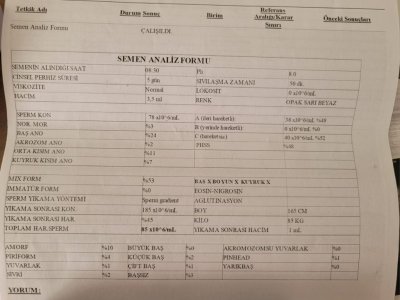

Semen analizi marmara eah'a ait.

Semen analizi marmara eah'a ait.